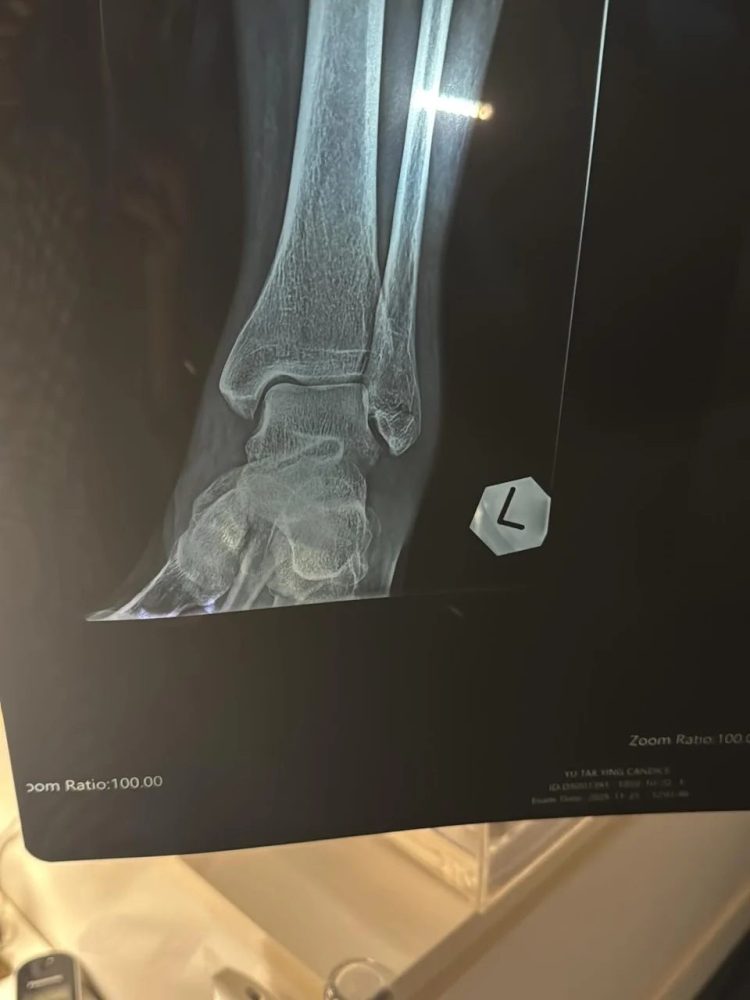

余安安表示,意外发生在 两星期前,她笑称:“咁大个女从未试过拗柴,两星期前终于试咗!”起初,她以为只是小伤,为了兑现陪孙仔看 圣诞灯饰 的承诺,仍硬撑出门,结果加重伤势。她说:“第二日痛到行唔到,就去睇中医。再过两日觉得唔多妥,就照了X-Ray🩻,原来骨裂咗😖。”

幸运的是,她的 脚踝骨未移位。照片中可见她左脚脚踝明显肿胀,如“猪蹄”般夸张,即使隔着屏幕都能感受到疼痛。为了保护脚部,她表示需要购买 “超贵嘅Boot” 并拄拐杖行走,但仍庆幸受伤的是左脚:“右脚最近仲可以揸到车!”